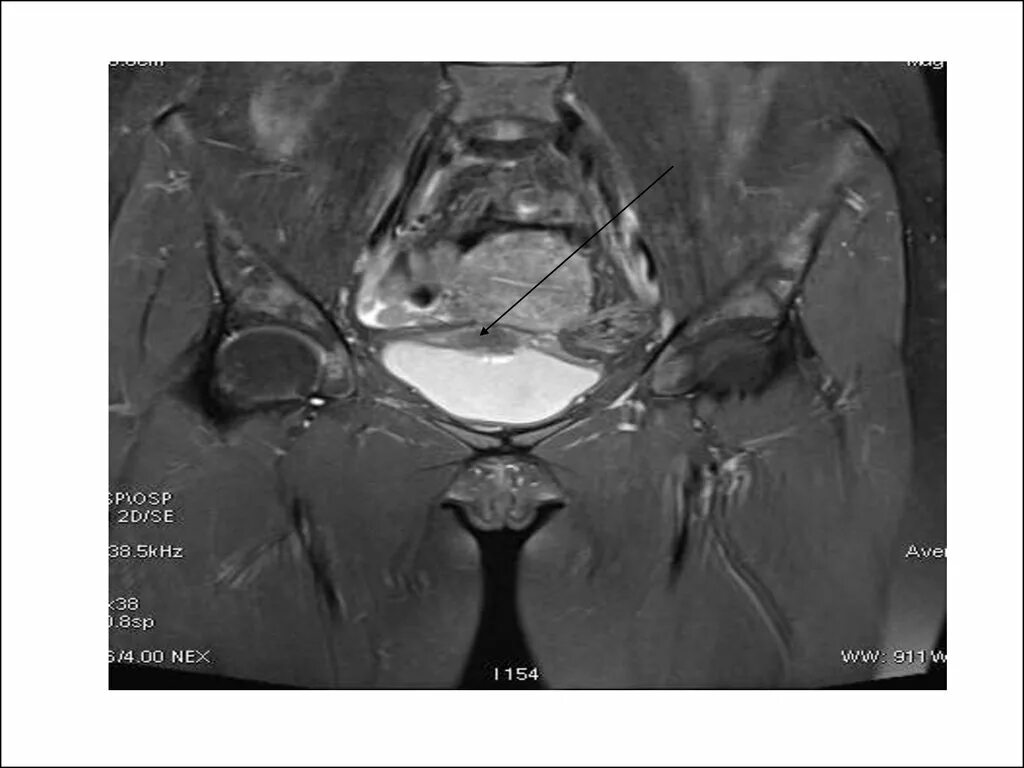

Образования малого таза мрт